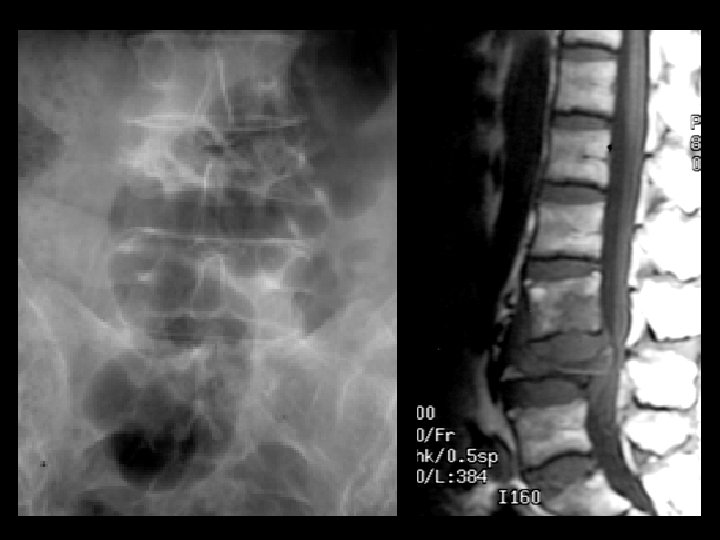

Potts Disease • Findings: – Complete collapse of L 4 and cauda equina compression – Subligamentous soft tissue extension to L 3 body • ddx: – Staph aurius – Gram negatives (IVDA)